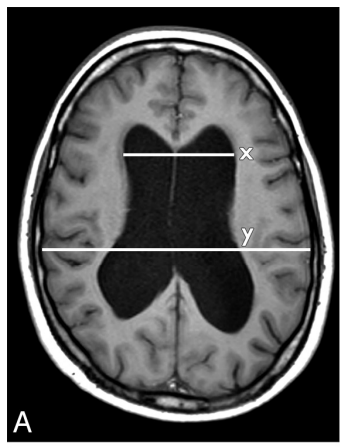

Features of Normal Pressure Hydrocephalus:

Evans Index >0.3 (x/y)

Callosal angle <90°

DESH ( disproportionately enlarged subarachnoid space hydrocephalus): Flattening of the cortical sulci in high convexity with widening of the sylvian fissure and ventricular dilation.